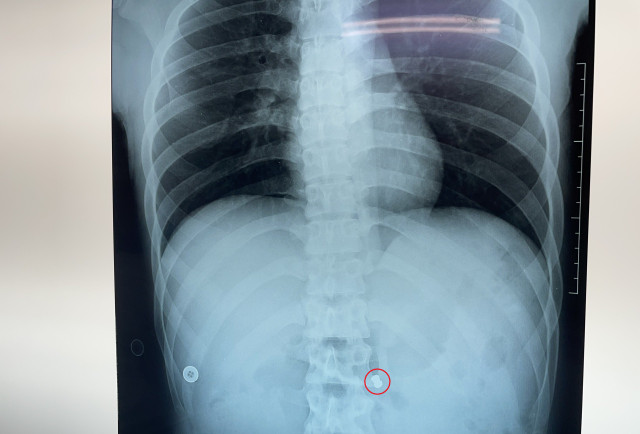

Kết quả chụp động mạch vành cho thấy bệnh nhân bị tắc động mạch mạn tính, ê-kíp tiến hành đặt stent tái thông mạch máu bị tắc. Sau can thiệp, tình trạng ổn định, mạch 106 lần/phút, huyết áp 138/69 mmHg.